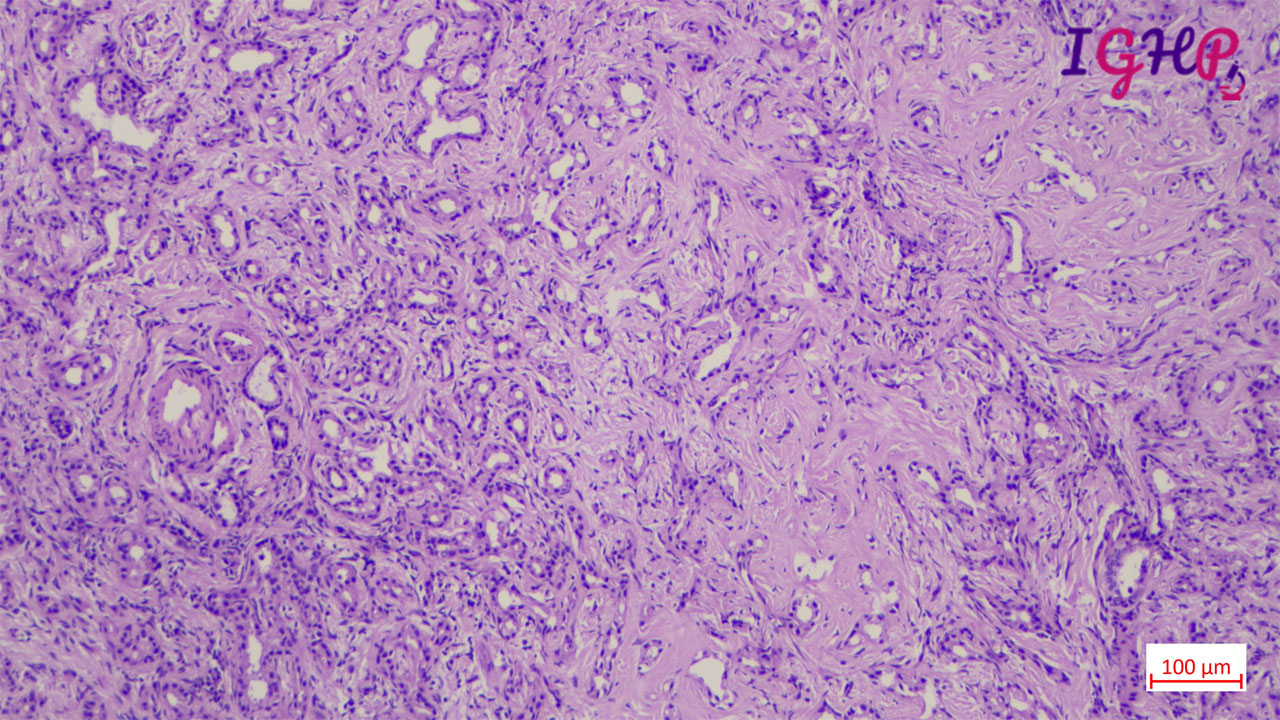

Microscopic examination showed an unencapsulated proliferation of uniformly spaced ductules lined by bland, cuboidal epithelium in a collagenous stroma. The architecture seems non-infiltrative, with evidence of entrapped native portal tracts present within the lesion itself.

BDA is an important diagnosis in frozen section examination. This needs to be differentiated from malignant nodules. Peripheral subcapsular location, presence of portal tracts within the lesion, inflammatory infiltrate and mild atypia favours a bile duct adenoma. Immunohistochemistrywith lowKi67 and wild type p53 may be used as adjunct.